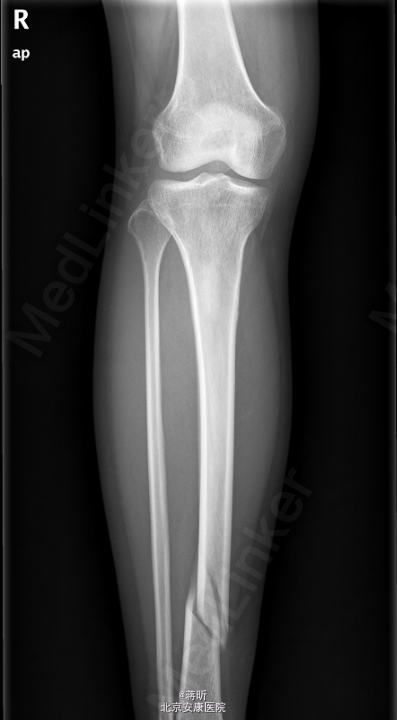

患者,女,32岁,因“右侧胫腓骨骨折术后1月余,发现下肢窦道1周”入院。 患者1月余前因外伤致右侧胫腓骨骨折,于2015-03-24在我院行“右胫骨骨折闭合复位内固定术+右腓骨骨折切复内固术”,术程顺利,术后恢复可,常规拍片复查,1周前自检发现右下肢膝关节处及外踝处出现窦道,伴流脓,无下肢麻木,无感觉异常,无发热寒战等其他不适,患者遂来我院就诊,门诊拟“骨折术后感染收住入院”。既往有“1型糖尿病”病史8年。

右小腿皮温稍高,右膝关节及踝关节活动未受限,右膝及右外踝处可见2处手术疤痕,分别长约7cm及5cm,愈合尚可,右膝正中及右外踝可见3处窦道,可见脓液流出,右足背动脉搏动可及,末梢各趾血循、感觉、活动正常。余肢体无殊。 2015-4-27我院拍片示:右胫骨中下段骨折术后复查。